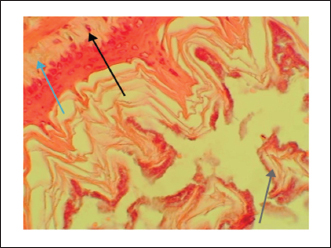

The gastric tissue slides were examined under a microscope for morphological changes such as hyperemia, hemorrhage, edema, necrosis, inflammatory changes, distortion, erosion, and ulcers caused by the destructive effects of indomethacin on stomach tissues. No pathological changes were observed in the normal control group (Fig. 1). Rats in the ulcer control group showed significant damage to the surface epithelium, necrotic areas penetrating the mucosal layer, and severe edema of the submucosal layer. Additionally, there was congestion with infiltration of inflammatory cells (Fig. 2). Histological results revealed that the treated rats with ranitidine had less protection of the gastric lining due to mild infiltration of leucocyte and edema in the submucosal layer, in addition to less disruption in both the superficial and deep mucosal layers. Treatment doses (300, 400 and 500 mg/kg) with P. farcta extract. Groups treated with P. farcta extract (300 and 400 mg/ kg) showed mild infiltration of inflammatory cells, edema, or significant disruption of the deep mucosa (Figs 5 and 6) while, P. farcta extract group (500mg/ kg) prevented histological changes and showed no infiltration of inflammatory cells, edema, or significant disruption of the deep mucosa (Figs 3, 4 and 7).

Fig. 1. Gastric mucosa lesion in rats; G1 served as control group; G2 served as ulcer control with indomethacin have sever injuries; G3, G4 and G5 received extract of Prosopis farcta at 300,400 and 500 mg/kg; G6 served as standard control with Ranitidine.

Fig. 3. Ulcer control group damage (↗) to the epithelium, necrotic areas penetrating the mucosal layer, and (↗) severe edema of the sub-mucosal layer with congestion and (↗) infiltration of inflammatory cells

Fig. 5. Prosopis farcta extract (300mg/kg) mild (↗) filtration of inflammatory cell, (↗) edema or less (↗) disruption in both the superficial and deep mucosal layers

Fig. 6. Prosopis farcta extract (400mg/kg) mild (↗) filtration of inflammatory cell, (↗) edema or less (↗) disruption in both the superficial and deep mucosal layers

Fig. 7. Prosopis farcta extract (500 mg/kg) prevented histological changes, nofiltration of inflammatory cells, edema, or distruption of deepmucosa.